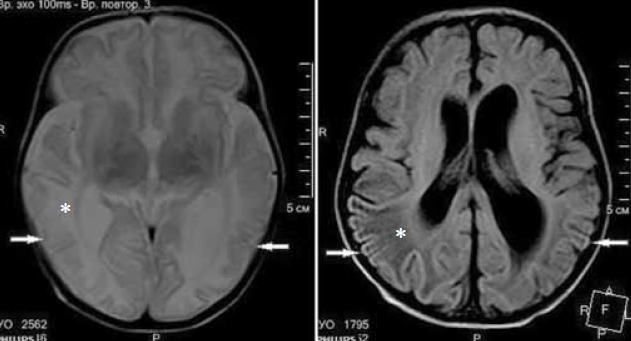

Выполнена магнитно-резонансная томография (МРТ) головного мозга через 3 недели после первого эпизода судорожных приступов (возраст ребенка на момент проведения исследования 6 недель) на аппарате Philips Ingenia1, 5 T. Получены Т1- Т2-взвешенные изображения, FLAIR-, DWI-изображения. На изображениях МРТ отмечаются зоны диффузных изменений МР-сигнала в теменно-затылочно-височных долях (рис. 6–8) без изменения архитектоники борозд и извилин. На представленных изображениях МРТ в аксиальной плоскости выявляются диффузные атрофические изменения коры головного мозга в затылочных долях, где толщина коры не превышает 1 мм, в сравнении с неизмененной корой в других отделах (рис. 6). На рис. 7 представлены изменения МР-сигнала (FLAIR) от измененной коры в теменно-затылочно-височных долях, без изменения архитектоники извилин. На DWI-картах сохраняются диффузные изменения МР-сигнала от структур затылочных долей, а также более отчетливо видны изменения сигнала от колена мозолистого тела (наконечник стрелки) (рис. 8).

Рис. 7. Аксиальная плоскость по протоколам Т2 и FLAIR соответственно. МРТ головного мозга ребенка в возрасте 6 недель с неонатальной гипогликемической энцефалопатией. Стрелками указаны изменения МР-сигнала от коры в теменно-височно-затылочных областях. Отмеченные звездочкой изменения МР-сигнала в белом веществе соответствуют этапу формирования головного мозга — терминальные зоны миелинизации